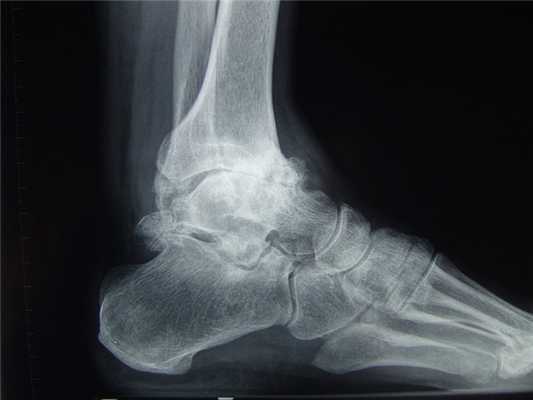

Остеоартроз голеностопного сустава на рентгене.

Остеоартроз левого(справа на снимке) голеностопного сустава

Артроз левого сустава. Суставная щель очень мала.